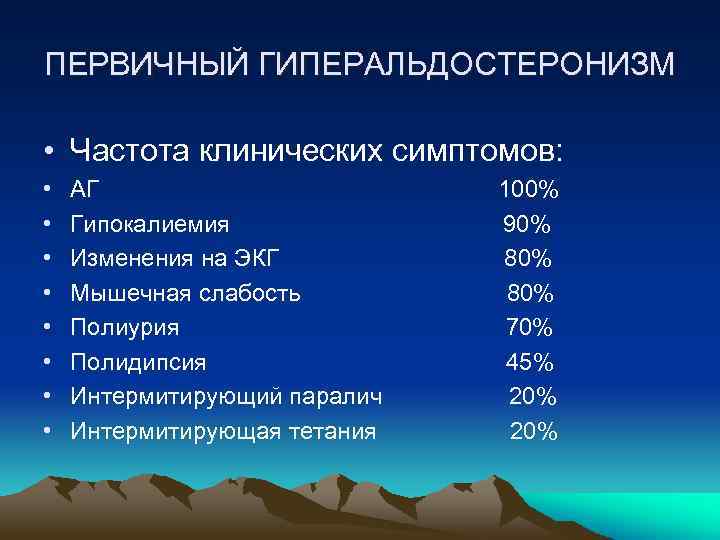

ПЕРВИЧНЫЙ ГИПЕРАЛЬДОСТЕРОНИЗМ • Частота клинических симптомов: • • АГ Гипокалиемия Изменения на ЭКГ Мышечная слабость Полиурия Полидипсия Интермитирующий паралич Интермитирующая тетания 100% 90% 80% 70% 45% 20%

ПЕРВИЧНЫЙ ГИПЕРАЛЬДОСТЕРОНИЗМ • Частота клинических симптомов: • • АГ Гипокалиемия Изменения на ЭКГ Мышечная слабость Полиурия Полидипсия Интермитирующий паралич Интермитирующая тетания 100% 90% 80% 70% 45% 20%